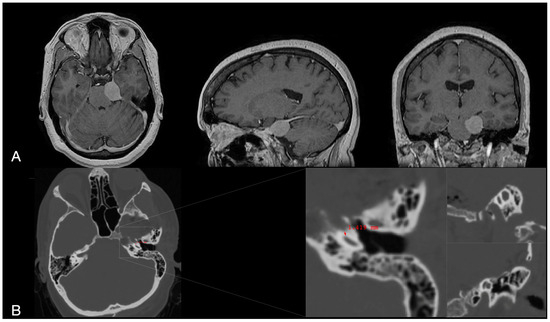

2.2. Clinical Case